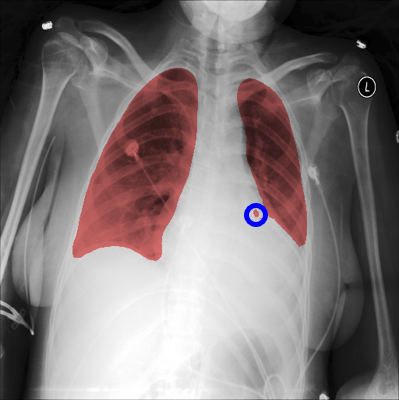

When applying a segmentation network, multiple regions may be returned as detected lung areas from each image. To complement the CBB, SA/LLA (Ratio of the smallest detected area to the largest detected area) and LA/LLA (Ratio of the second-largest detected area to the largest detected area) are used to evaluate lung lobe detection. Ideally, a reliable automated lung segmentation approach must find two complete lung lobes (i.e., two regions). In this case, (LA/LLA) and (SA/LLA) will be identical. Fig. 5 illustrates (LA/LLA) as a function of (SA/LLA). Commonly for both methods, the majority of observations follow an identity function, which means the algorithms mostly found two lung lobes per image. For those observations that did not follow the identity function, the two methods behaved differently. The difference is mainly rooted in two scenarios. Fig. 6 shows an example of a detected lung region by the two networks in the same image. In challenging CXR images, the methods may find more than one region per lung lobe (XLSor, Fig. 6-b). In this scenario, the segmented area does not have a significant effect on the final boundary box. However, in the second scenario, the algorithm mistakenly selects another area excluding the lung lobes (e.g., other parts of the body or background) as part of the lung area (UNB, Fig. 6-a). In this scenario, the final bounding box may cover a larger area than the lung region. Although the segmentation approach would not cause any loss of information for the second scenario, it questions the main purpose of lung segmentation (i.e., removing irrelevant regions and accurate localization of the lung area). As illustrated in Fig. 5, while XLSor mostly followed the first scenario, UNB followed the second one. Therefore, XLSor is a better segmentation network than UNB.

Refer to caption

Fig.6: Example of detected lung region by the two networks in the same image (a: UNB, b: XLSor).